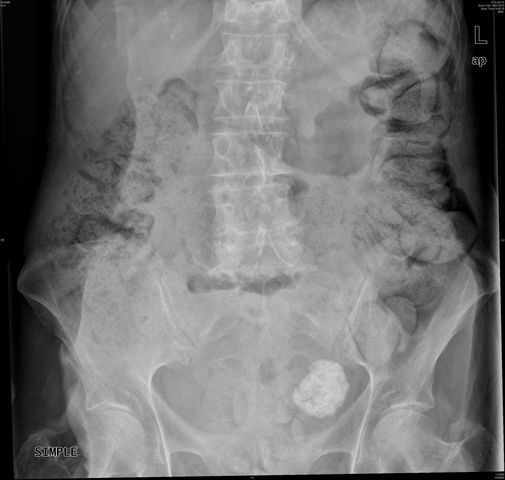

APR Cálculo renal coraliforme